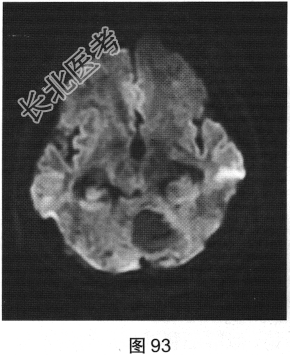

- [材料题] 患者女性,51岁,因“头晕、恶心进行性加重1个月余,伴呕吐5小时”就诊。患者于1个月前出现头晕症状,伴恶心,无视物旋转、头痛、走路不稳,无言语改变、意识障碍。患者症状反复发作并进行性加重,2周前间断出现走路不稳,似醉酒样步态,倒向左侧;5小时前出现头晕、恶心,并呕吐胃内容物,站立不稳。既往有高血压病史3年,血压控制尚可。查体:轮椅推入病房,可见步态不稳,神志清楚,应答正确,无吟诗样及爆炸样言语,遵嘱活动,双侧瞳孔等大正圆,对光反射灵敏,四肢活动可,肌力、肌张力未及异常,指鼻试验、双侧轮替试验阴性,双侧跟膝胫试验欠稳准,双侧膝反射及跟腱反射正常,双侧病理征未引出,闭目难立征不能配合。实验室检查:外周血白细胞计数15.29×109/L,中性粒细胞百分比92.1%,二氧化碳18.8mmol/L,血糖7.05mmol/L;心肌酶、凝血试验正常。

- 多项选择题2.[提示]患者行CT及MRI检查,如图90~图95所示。CT及MRI上的阳性影像学表现包括( )

A、MRI示右侧囊实性病变

B、病变实性成分增强扫描可见明显强化

C、MRI示左侧囊实性病变

- 多项选择题3.根据患者病史及影像学检查,提示其可能诊断为( )

A、血管母细胞瘤

E、脑视网膜血管瘤病